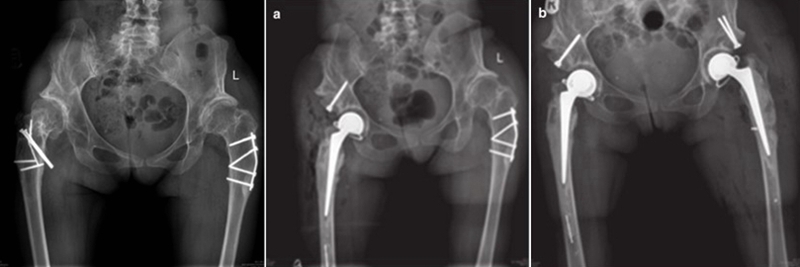

导致股骨近端畸形的原因主要有原发型和继发型两大类。原发型多为发育异常所致(DDH)、代谢性骨病、强直性脊柱炎引起;继发型主要为手术所致,包括股骨近端截骨术、股骨近端骨折内固定术、全髋或半髋置换,其他因素如感染、创伤畸形愈合等。

目前临床上对于股骨近端畸形的处理,仍是关节外科的难题之一,在处理时常面临以下挑战:①费时、费力、费脑子;②手术复杂,时间长,并发症高;③特殊假体;④多种畸形同时矫正不易;⑤截骨重建困难、骨折愈合难;⑥股骨近端开口位置错误,股骨穿孔或骨折,假体柄非中心安置;⑦臀中肌张力不易调整;⑧并发症:撞击、关节不稳、反复脱位、远期松动等。

三、手术策略及处理

手术的核心思想:恢复旋转中心、恢复下肢长度、恢复肌肉张力。